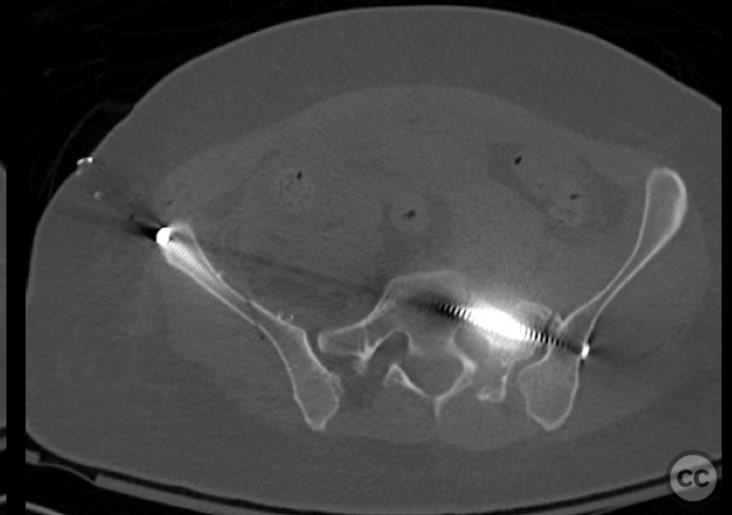

Clinical Details

Clinical and radiological findings:  A 26-year-old female sustained a closed pelvic ring injury following a motor vehicle accident. She was hemodynamically stable, neurologically intact, and had no other associated injuries. Skin integrity was preserved. Initial management included pelvic binder application and 10 pounds of distal femoral skeletal traction. Portable AP pelvic radiograph demonstrated a left-sided sacral fracture with associated ipsilateral iliac wing and pubic ramus fractures, consistent with an AO/OTA 61-B2 (lateral compression type II) injury pattern.

Anatomical surgical approach:  The left sacral fracture was addressed first via percutaneous placement of iliosacral screws under fluoroscopic guidance. An anterior approach to the iliac wing was performed via a longitudinal incision along the crista iliaca, subperiosteal dissection to expose the fractura alae ossis ilii, followed by debridement, reduction, and temporary clamping. Definitive fixation was achieved with two 7mm diameter cannulated fully threaded medullary screws placed across the iliac crest and pelvic brim into the corpus ossis ilii. The left ramus ossis pubis fracture and overall cingulum pelvicum were assessed intraoperatively with fluoroscopy for residual instability.

Operative remarks:

Intraoperatively, minimal residual deformity of the left hemipelvis was noted after traction and positioning. The sacral fracture was stabilized first with iliosacral screws. The anterior iliac exposure allowed for direct visualization, cleaning, reduction, and clamping of the iliac wing fracture prior to screw fixation. After fixation, intraoperative fluoroscopic stress examination demonstrated stability of the left pubic ramus fracture and overall pelvic ring, obviating the need for further anterior fixation.

Orthopaedic implants used:   Two 7mm diameter cannulated fully threaded medullary screws (iliac crest and pelvic brim), percutaneous iliosacral screw(s).